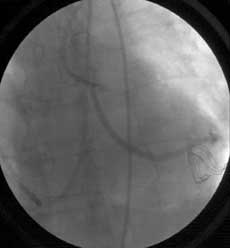

冠狀繞道手術完成之後,依據國外先前的研究,約有2~6%會需要立即作手術的 修正。 本院在大量採行技術難度較高的心臟不停跳冠狀動脈繞道手術之時,秉持著堅持最高品質的信念,引進進步的手術室血管攝影設備, 立刻以血管攝影進行血管 暢通性的評估(completion coronary angiography),以便偵測任何縫合處的的缺陷,並立即作修正。

目前為止,本院手術後即時血管攝影的研究顯示,本院的手術後即時血管暢通率極佳,只有不到 2%的繞道手術吻合處需要作修正,這樣的結果優於許多國外的報告。

使用手術室血管攝影系統

一旦完成繞道手術後就用血管攝影來確認縫合處的品質